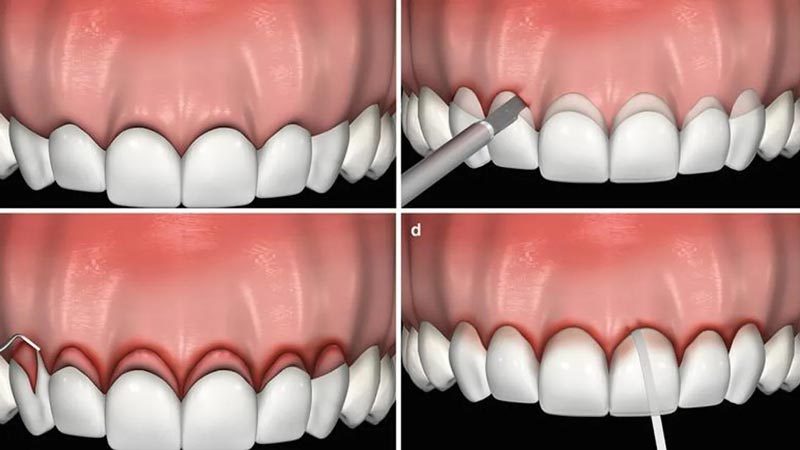

فرآیند لیفت لثه برای کامپوزیت دندان معمولاً با معاینه اولیه توسط دندانپزشک آغاز میشود تا نیاز به اصلاح خط لثه و نوع درمان مشخص شود. این فرآیند در بیشتر موارد به صورت سرپایی و با استفاده از بی حسی موضعی انجام میشود تا بیمار در طول درمان احساس راحتی داشته باشد. در مرحله اول، دندانپزشک با استفاده از ابزارهای جراحی، لیزر یا تکنیک های پیشرفته دیگر، بافت اضافی لثه را برداشته و خط لثه را به شکلی متقارن و دلخواه اصلاح میکند.

پس از اصلاح خط لثه، دندانها بیشتر نمایان میشوند و ظاهر متناسب تری پیدا میکنند. متخصص کامپوزیت معمولاً پس از اتمام لیفت، کمی زمان برای بهبود بافت لثه در نظر می گیرد و سپس فرآیند کامپوزیت دندان را آغاز میکند. این روش نه تنها به بهبود نتیجه نهایی درمان کمک میکند، بلکه به لبخندی طبیعی تر و زیباتر منجر میشود. برای انجام لیفت لثه قبل از کامپوزیت دندان و اینکه آیا کاندیدای لیفت لثه قبل از کامپوزیت دندان هستید یا خیر، کافی است از طریق پر کردن فرم با ما ارتباط برقرار کنید.